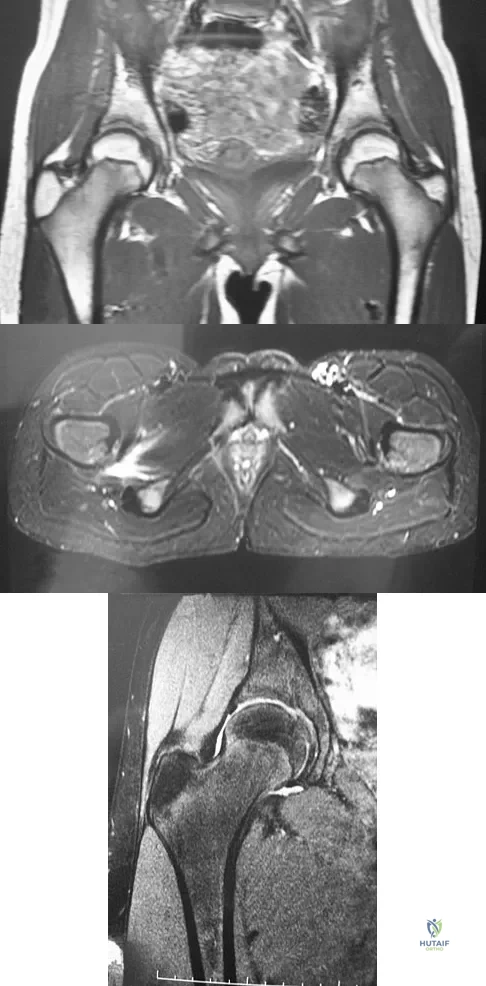

A 15-year-old girl who swims the breaststroke has had hip pain after training excessively for a national level competition. Based on the MRI scans shown in Figures 5a through 5c, what is the most likely diagnosis?